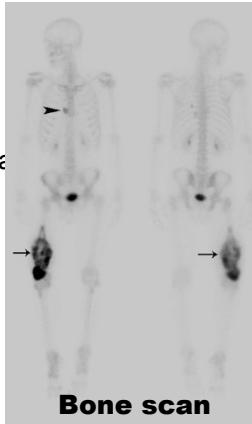

- Bone Scan - detection of bone metastases

- Systemic staging - evaluation for regional and distant metastases (CT chest, bone scan, PET scan)